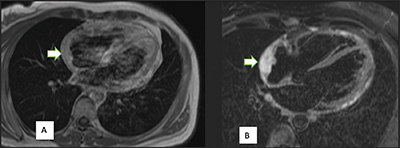

Figure 2

Right atrium angiosarcoma, a broad-based mass in the right atrium associated with thickening of the pericardium, is predominantly isointense to the myocardium on the T1-weighted image (arrow) (A). On the T2-weighted image (B), the mass shows a typical hyperintensity (arrow).